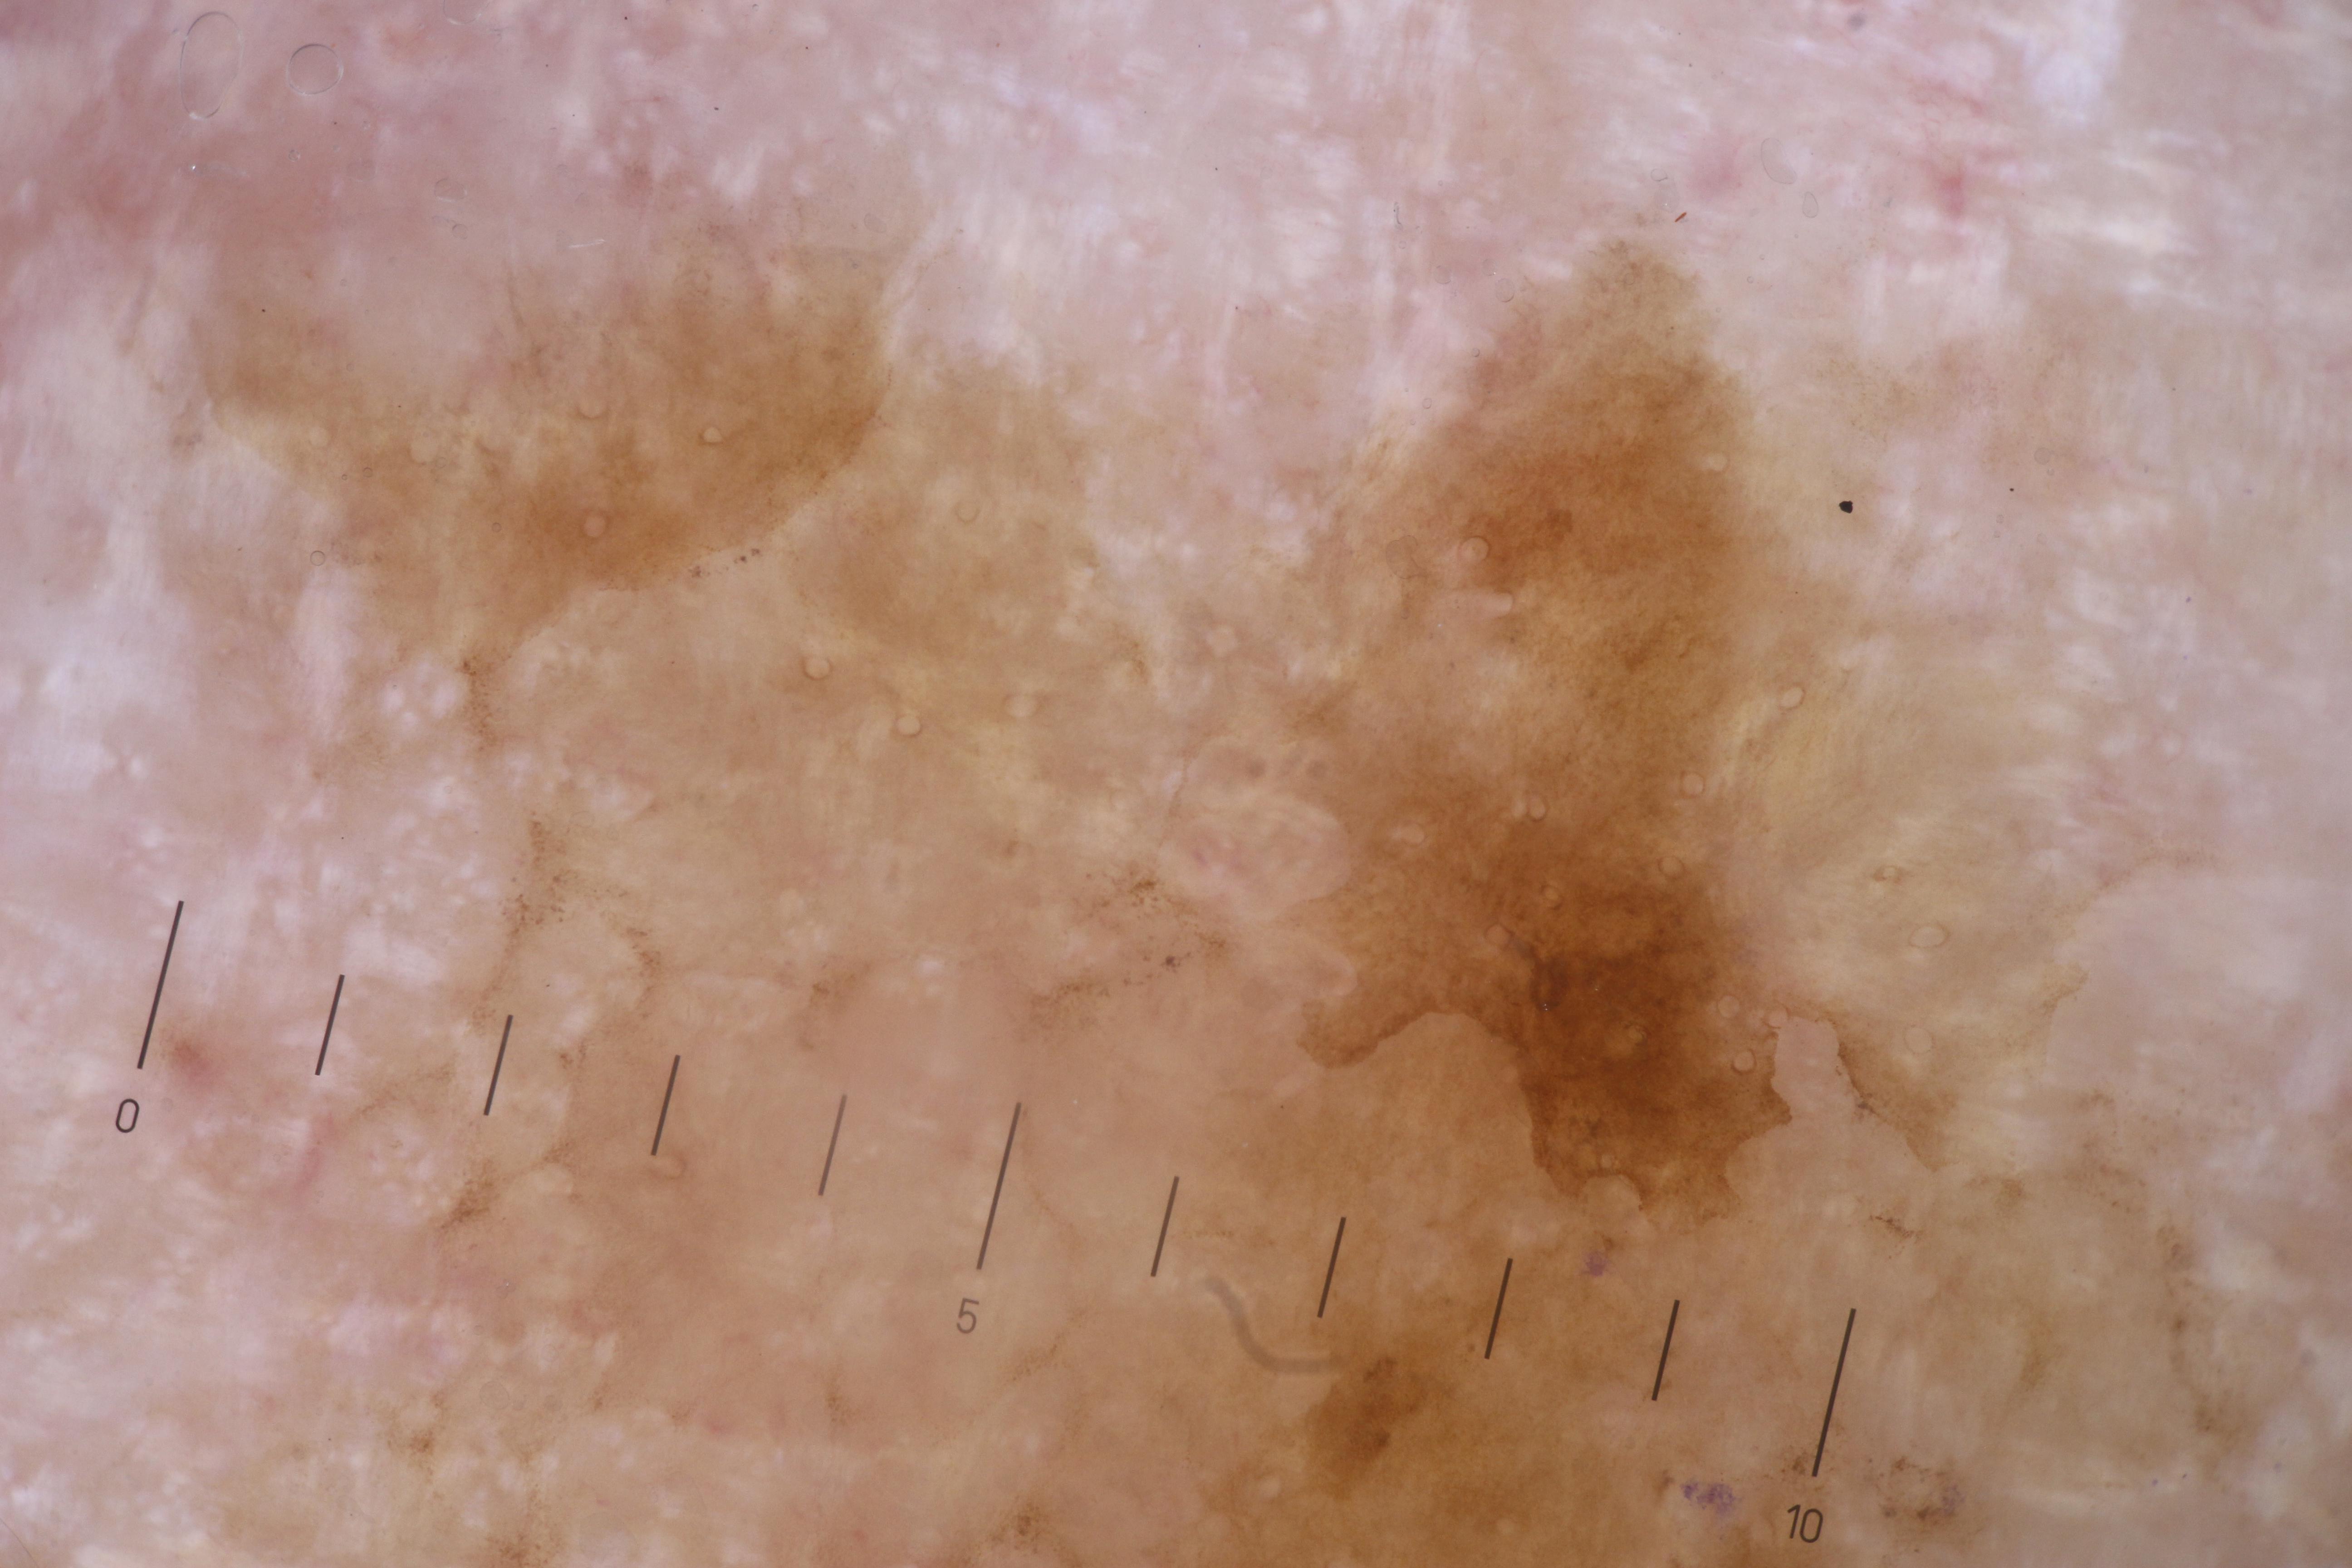

{

"age_approx": 80,

"anatom_site_general": "head/neck",

"concomitant_biopsy": false,

"diagnosis_1": "Benign",

"diagnosis_confirm_type": "serial imaging showing no change",

"fitzpatrick_skin_type": "I",

"image_type": "dermoscopic",

"lesion_id": "IL_8742560",

"patient_id": "IP_7037594",

"sex": "male"

}